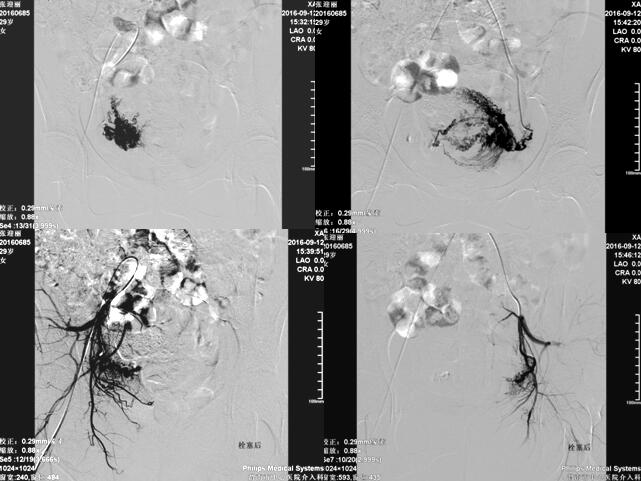

乐鱼手机站入口介入科在李建国主任带领下自2006年开展子宫肌瘤栓塞术,现已完成数百例相关疾病介入治疗,为渭南地区及各县患者提供了全新的子宫肌瘤治疗方法,避免患者子宫全切。子宫肌瘤栓塞术是一种安全有效的治疗方法,是由介入医生经病人腹股沟股动脉导入一导管至肌瘤的血供(子宫动脉)处,释放一些细微颗粒,弹簧圈、或者球囊等阻断肌瘤的血供、供养及出血部位,使肌瘤纤维化,出血停止,肌瘤萎缩。所有经过介入治疗的患者术后大约3-6个月相关症状完全消失。

经子宫动脉栓塞术还可应用于子宫腺肌症、胎盘植入、瘢痕妊娠、前置胎盘及产后大出血等疾病,以下为一例产后大出血患者介入治疗图片: